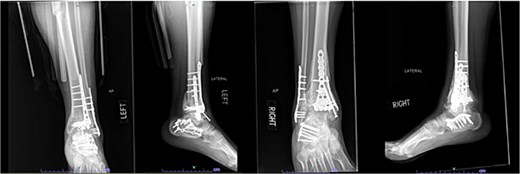

A 38-year-old male with a BMI of 27.5 kg/m2 and a history of alcohol use disorder, paranoid schizophrenia, smoking, and prior bilateral calcaneal fractures treated with ORIF 4 years earlier sustained bilateral pilon fractures after jumping from a third-story window (Fig. 3). He presented to the hospital 5 days after injury.

AP and oblique radiographs of patient 2 obtained after a fall, demonstrating bilateral pilon fractures and retained hardware from prior bilateral calcaneal ORIF.